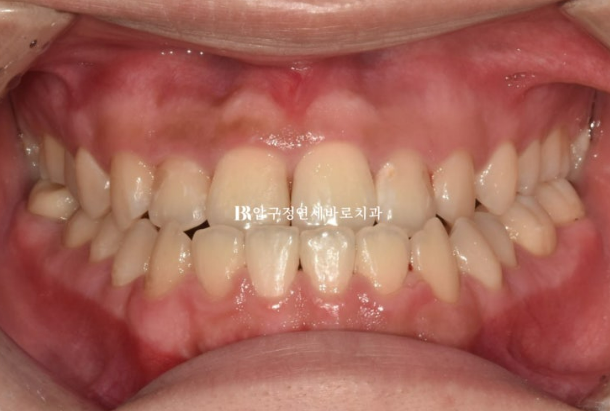

양악수술을 고려 중인 환자분이 내원하셨습니다.

양악수술 병원은 이미 여러군데 비교상담을 다녀오셨고

수술교정은 인비절라인으로 하고 싶다며 내원하셨습니다.

23.07

반대교합과 주걱턱이 심한 겨웅여서 양악수술 없이는 교정이 불가능한 상황입니다.

이 부분은 환자분도 알고계셨습니다.